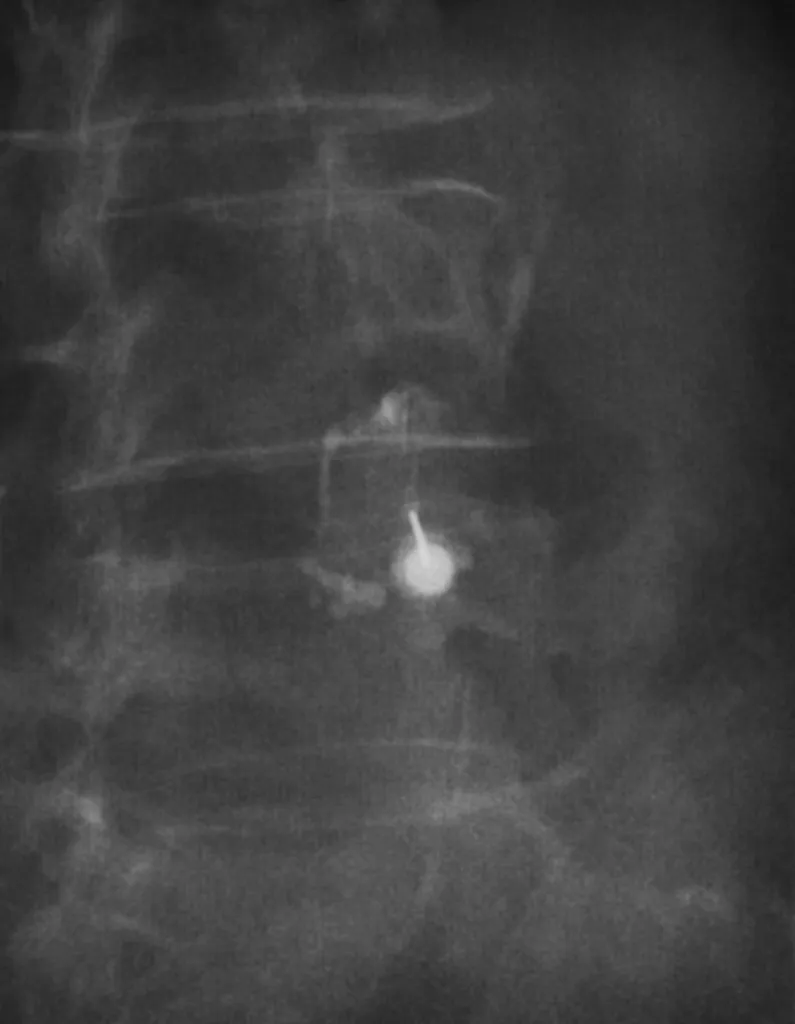

Infiltration sacro-iliaque scannerisée pour sciatalgie à prédominance mécanique à Aubagne

L’infiltration sacro-iliaque scannerisée est une solution précise et efficace pour traiter la sciatalgie à prédominance mécanique chez les patients d’Aubagne. Grâce à l’imagerie médicalisée, cette technique permet un soulagement ciblé de la douleur lombaire ainsi qu’une amélioration notable de la ...

Infiltration articulaire postérieure sous contrôle scopique à Marseille

Nos centre d'imagerie médicale Marseille Lodi, La Rose et Fuveau réalent les infiltrations articulaire postérieure sous contrôle radiographique. Après avoir nettoyé la peau, nous positionnons une aiguille au niveau d'une des articulations postérieures de la colonne vertébrale. Une anesthésie est r...